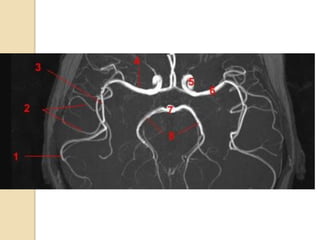

Arteries of the brain (cranial view) - MRA

1. Anterior cerebral artery

2. Anterior communicating artery

3. Basilar artery

4. branches (in insula) of middle

cerebral artery

5. Cavernous portion of internal

carotid artery

6. Cervical portion of internal carotid

artery

7. Genu of middle cerebral artery

8. Intracranial (supraclinoid) internal

9. Middle cerebral artery

10. Ophthalmic artery

11. Petrous portion of internal carotid

12. Posterior cerebral artery

13. Posterior cerebral artery in ambient

cistern

14. posterior cerebral artery in

interpeduncular cistern

15. Posterior communicating artery

16. Posterior inf cerebellar artery.

17. Quadrigeminal portion of posterior

18. Superior cerebellar artery

19. Vertebral artery